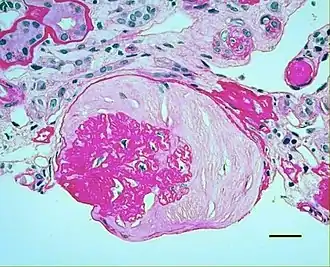

| Micrograph showing renal arterial hyalinosis – pink ring right-of-centre. PAS stain. | |

In benign nephrosclerosis, the changes occurring are gradual and progressive, however, there can be sufficient kidney reserve capacity to maintain adequate kidney function for many years.[10] The large renal arteries exhibit intimal thickening, medial hypertrophy, duplication of the elastic layer. The changes in small arterioles include hyaline arteriolosclerosis (deposition of hyaline, collagenous material), which causes glomerular collapse (wrinkling and thickening of capillary basement membranes and collapse of capillary lumen) and solidification (glomeruli exhibit sclerosis and increase in mesangial matrix). The degree of scarring correlates with the degree of glomerular filtration deficit.